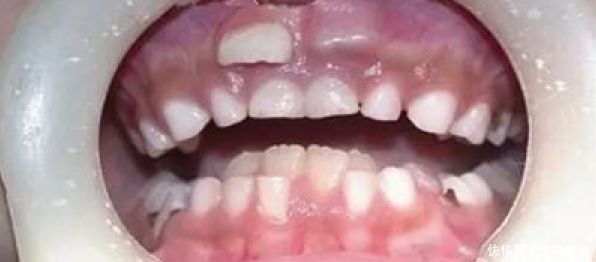

1近年来,一些孩子在换牙时乳牙还没有脱落,新牙就从里面冒了出来形成双排牙的现象越来越多。

这位来自姑苏的妈妈同样有这样的烦恼,儿子到了换牙期,他却一直没动静,直到8岁才出现换牙迹象,由于乳牙沒有及時脫落,下门牙竟然出现了前后“双排牙”,看着十分吓人。

从合肥市口腔医院的统计显示,如今“双排牙”已成为常见的儿童口腔疾病之一,要占到儿童口腔疾病30%左右,在临床上发生率已高达10%。近年来,越来越多的孩子出现双排牙,这种现象被称为乳牙滞留。孩子长双排牙跟日常饮食有很大的关系。家长害怕孩子咀嚼费劲和吸收能力差,为了方便喂养,从小给孩子吃的食物特别精细软烂,水果榨成汁,排骨剃下骨,大米只喝粥,结果使牙齿使用率低,生理磨耗少,造成乳牙不能及时脱落的情况。此外,营养供给过剩也会造成孩子牙胚发育早,乳牙还没脱落,恒牙却已经长出来了。同时,也存在孩子乳牙出现龋坏,甚至牙根发生病变,导致牙槽骨与牙根粘连,使乳牙牙根未吸收或吸收不完全,也造成乳牙不能及时脱落的情况。乳牙滞留有哪些危害?乳牙滞留会造成恒牙异位萌出,导致牙齿排列不齐,影响正常咬合,抑制颌骨发育,影响孩子的面型和美观;不利于孩子清洁牙齿,容易食物嵌塞,造成口臭,影响口腔卫生。乳牙残根残冠滞留,容易损伤口腔黏膜,造成细菌感染,增加患龋齿的风险。如何预防双排牙?建议家长给孩子多吃耐嚼质硬的食物。孩子在生长发育阶段,家长要循序渐进地给孩子吃一些硬度适中、可撕拽的食物,例如可以给孩子吃苹果、甘蔗、玉米、花生等耐嚼的食物,这样可以保持对乳牙良好的刺激作用,促使乳牙按时脱落。如果家长发现孩子口腔出现双排牙,一定要带孩子到正规医院检查,经医生检查确定乳牙下方有恒牙胚或者恒牙已经萌出,在孩子身体适宜拔牙的情况下,最好及早拔除。